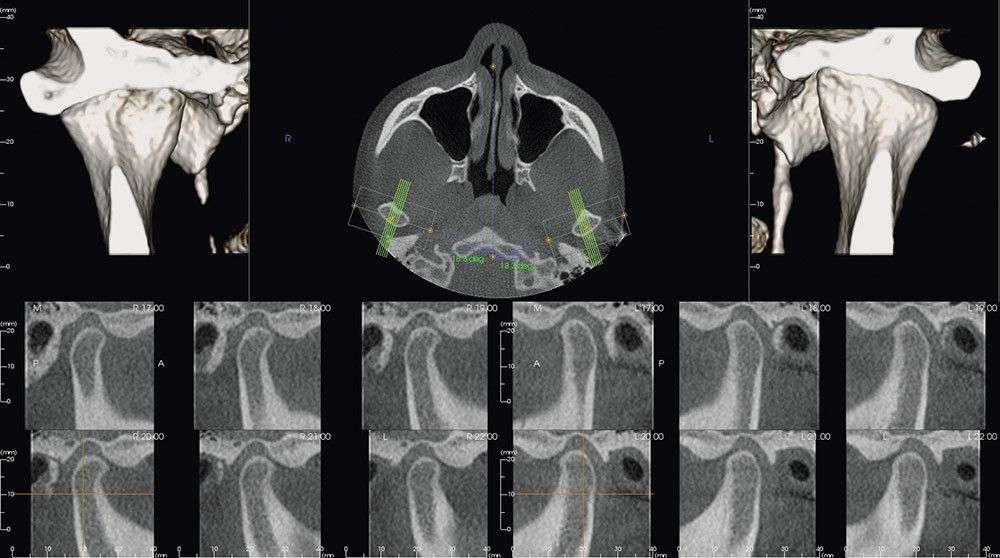

Гнатология: индивидуальная диагностика ВНЧС